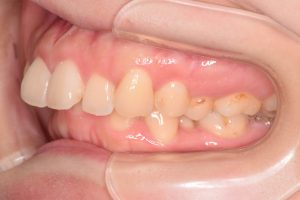

右側

0000000009

0000000137